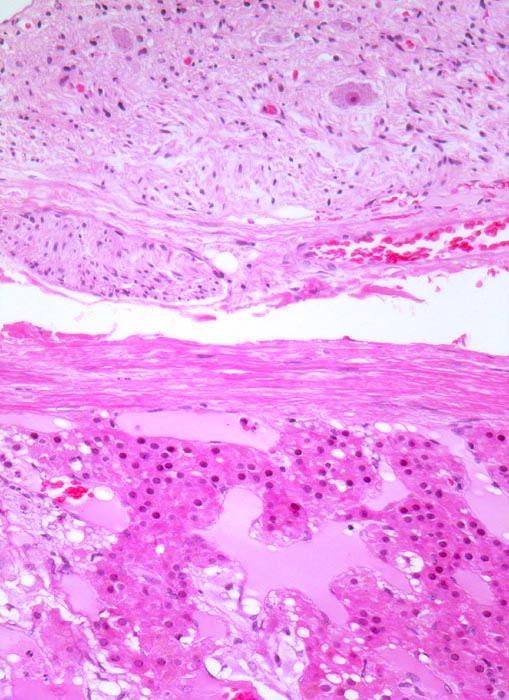

• Unscharf begrenzter, gefässreicher Tumor ausgehend vom Nebennierenmark.

• Zungenförmige Infiltration der angrenzenden Nebennierenrinde. Die Zellen der Nebennierenrinde haben reichlich eosinophiles Zytoplasma und kleinere Kerne als die Tumorzellen.